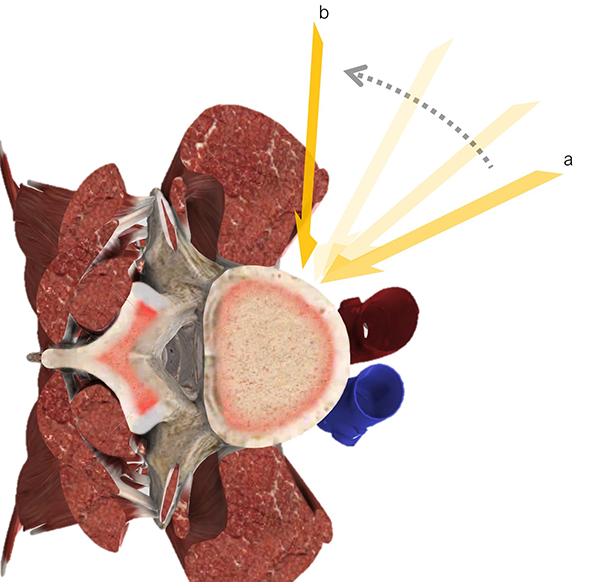

Figura 1: Representación esquemática de los abordajes anterolaterales al disco intervertebral. ALIF, fusión lumbar intersomática anterior; OLIF, fusión lumbar intersomática oblicua; LLIF, fusión lumbar intersomática lateral.

Existen múltiples vías de abordaje para acceder al espacio discal y realizar una LIF. Las técnicas por vía posterior incluyen la fusión intersomática posterior (PLIF), transforaminal (TLIF) y extra foraminal (ELIF).1 Las técnicas anterolaterales (Figura 1) incluyen la fusión lumbar intersomática anterior (ALIF, por sus siglas en inglés) y la vía lateral transpsoas (LLIF, por sus siglas en ingles). Si bien estas últimas técnicas han sido descriptas en forma reciente, han ganado cada vez más importancia en el arsenal terapéutico del cirujano de columna.2,3

Figura 1: Representación esquemática de los abordajes anterolaterales al disco intervertebral. ALIF, fusión lumbar intersomática anterior; OLIF, fusión lumbar intersomática oblicua; LLIF, fusión lumbar intersomática lateral.